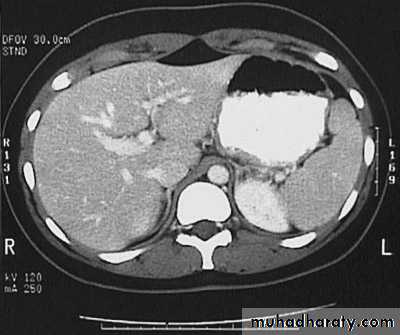

Hydatid cyst

Appear as large oval hypo dense area density of fluid with well defined margin , sometime at their periphery multiple flecks of calcification are seen at their periphery .

Hydatid cyst with daughter cyst , appear as multiple hypo densities rounded area within the main loculi with multiple rim of

calcification

Hydatid cyst within the liver

CT Scane